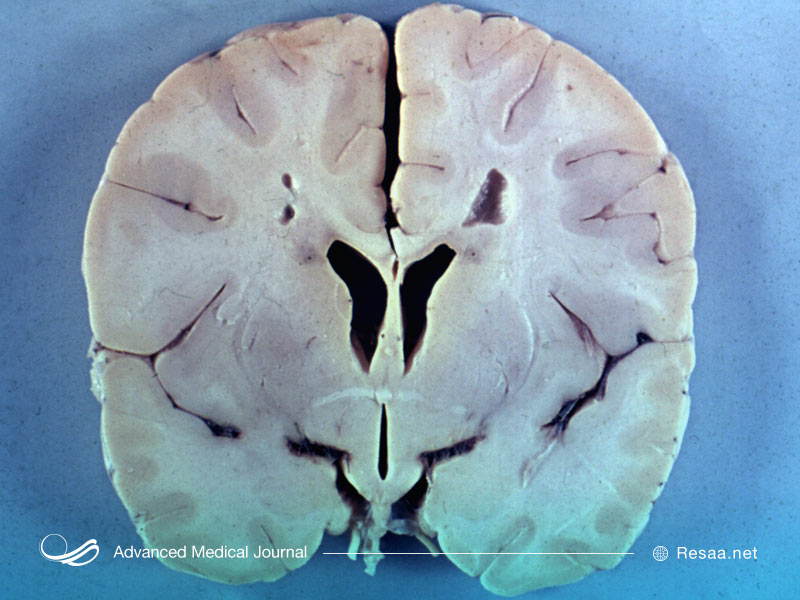

نوع بزرگسالی بیماری الكساندر كمترین شیوع را دارد و با كندی پیشرفت میكند. تقریباً 6٪ موارد اختلال، این مدل از بیماری را نشان میدهند. به دلیل ماهیت ارائه الیاف روزنتال در بیماری الكساندر، برخی از موارد بیماری با شروع بزرگسالی فقط در هنگام كالبد شکافی و به طور تصادفی کشف میشود.

این موضوع بسیار نادر است که بیماری الکساندر در اواخر زندگی فرد ایجاد شود. اگر چنین شود، اغلب علائم بیماری با علائم مولتیپل اسکلروزیس “multiple sclerosis” یا تومور مغزی “brain tumor” اشتباه میشود. به طور معمول شدت بیماری در این موارد به قدری خفیف است که بیماری الکساندر پس از مرگ تشخیص داده میشود، دقیقا زمانی که کالبد شکافی رسوبات غیرمعمول پروتئین را در مغز نشان میدهد.